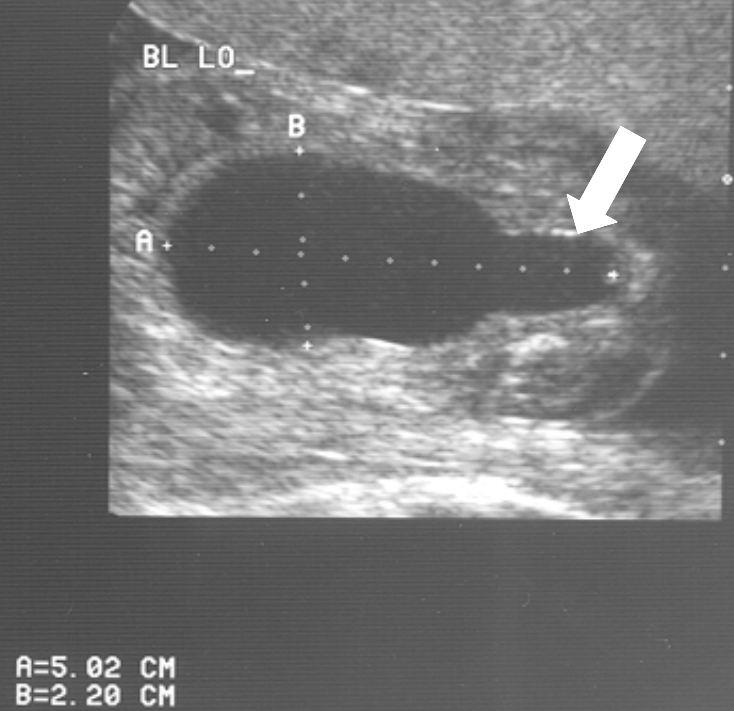

Diagnose vóór de geboorte

Veel ernstige vormen van urethrakleppen worden al gezien bij echografisch onderzoek vóór de geboorte. Bij de 20 weken echo (of misschien in de toekomst bij een 13 weken echo) worden verwijde nierbekkens en urineleiders gezien. De blaas kan dikwandig zijn, maar ook zeer groot en uitgerekt. Vaak kan het verwijde deel van de plasbuis ónder de blaas worden gezien. Dat noemen we het “sleutelgat teken” omdat de blaas in lengtedoorsnede op de echo er dan uitziet als een sleutelgat. De hoeveelheid vruchtwater kan normaal of verminderd zijn. Als er een verdenking is op urethrakleppen wordt de bevalling gedaan in een centrum waar direct optimale zorg kan worden geleverd aan de pasgeborene.

20 weken echografie: links: dikwandige blaas met verwijding van de plasbuis tot aan de kleppen (pijl): het “sleutelgat teken”. Onder: verwijde urineleiders. Bij kinderen gaan de urineleiders bij verwijding ook erg gekronkeld verlopen.